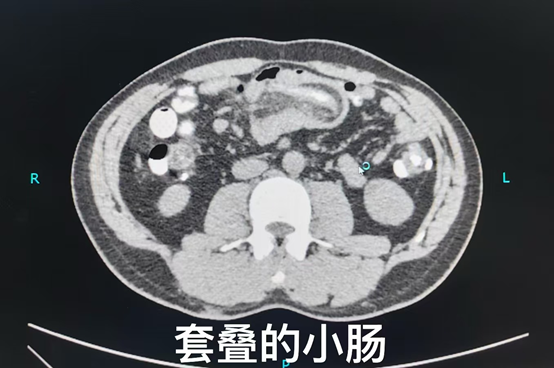

普外/肿瘤外科副主任医师叶晋生接到通知后第一时间赶到急诊科,详细了解病史、进行查体,并完善盆腔CT提示肠系膜脂肪及血管进入肠腔上游部分,肠腔内可见气液平面,明确诊断郑先生出现了肠套叠。普外/肿瘤外科主任路夷平考虑到郑先生肠套叠已诱发肠梗阻表现,立即给予禁食水、下胃管胃肠减压、补液等对症治疗,并告知郑先生需要尽快手术。当得知可能需要切除一部分小肠时,郑先生的内心充满焦虑与恐慌。他害怕手术会带来各种并发症,担心自己以后无法正常工作,无法照顾家人。普外/肿瘤外科医疗团队为郑先生制定了详细的治疗方案并耐心地向郑先生解释病情和治疗方案,安抚他的恐惧情绪。“医生们都特别耐心,跟我讲了很多关于手术的事情,让我心里有了底,也没那么害怕了。”郑先生说道。

普外/肿瘤外科副主任叶晋生带领刘鹏医师、刘一博医师和王洁医师顺利完成了腹腔镜微创手术,解决病变的同时保证了肠道的通畅。术后,郑先生在医护人员的悉心照料下,恢复得十分顺利,很快就出院了。如今,他的腹痛症状消失,进食排便都恢复了正常,日常生活不再被疼痛困扰。